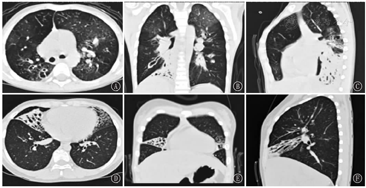

26例患儿均在随访过程中复查HRCT发现支气管扩张(图1),20例患儿HRCT同时存在"马赛克征",即PIBO,其中8例患儿存在不同程度的肺实变,5例患儿存在纤维条索影,3例患儿存在胸膜增厚,2例患儿存在肺囊泡。其中20例合并PIBO的支气管扩张患儿急性期肺实变累及范围均≥2个肺叶(20/20,100%)。24例(92.30%)为弥漫性支气管扩张(即>2个肺叶),HRCT显示支气管扩张最常累及左下叶、右下叶(各21例,80.77%),其次为右上叶(17例,65.38%),最后为右中叶、左上叶(各15例,57.69%)。20例合并PIBO的支气管扩张症患儿均为弥漫性支气管扩张。支气管扩张的类型以柱状最常见(23例,88.46%),其次为柱状-囊状并存(2例,7.69%),单纯囊状仅1例(3.85%)。

注:HRCT:高分辨率CT;PIBO:感染后闭塞性细支气管炎 HRCT:high resolution computed tomography;PIBO:post-infectious bronchiolitis obliterans